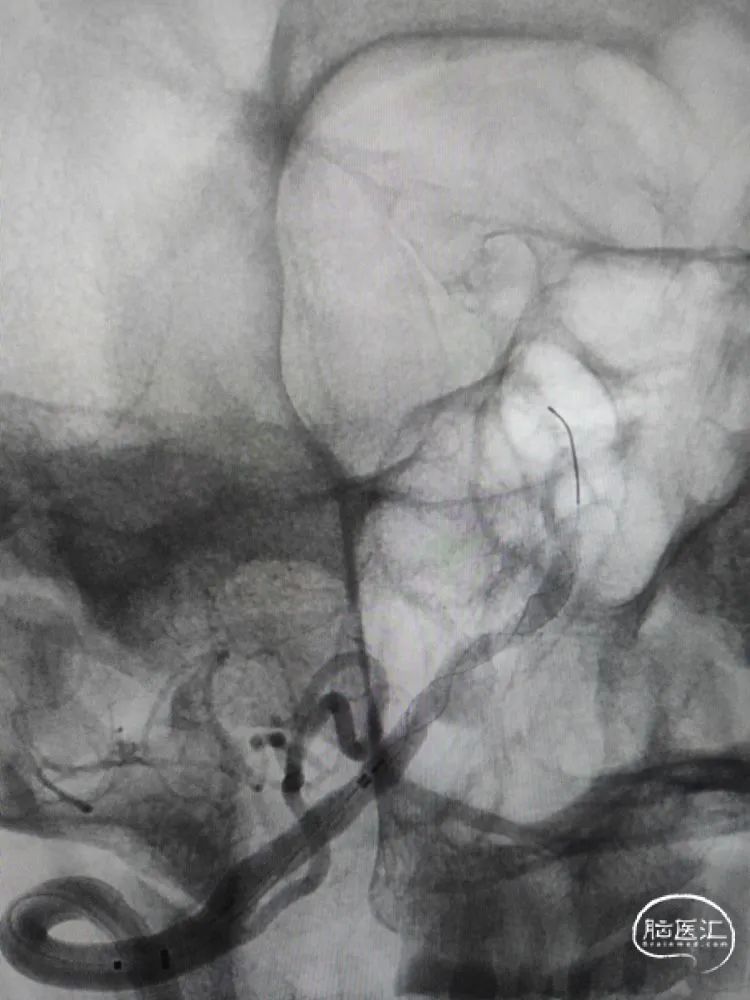

改进版的Tubridge血流导向密网支架到位后,支架在远端预打开再回撤定位,从双椎动脉汇合处下方开始释放,缓慢推出支架进行头端锚定,改进版的Tubridge血流导向密网支架有效改善了头端打开和锚定性能,支架远端刚好落在汇合处下方,造影观察支架充分锚定后,继续缓慢释放支架至瘤颈中段,造影确认后,随后等张释放支架完毕,支架完全覆盖动脉瘤。改进版的Tubridge血流导向密网支架优化了编织丝和编织密度,支架支撑力显著提升,支架打开效果优异,全段充分张开贴壁。

正侧位造影以及三维重建提示动脉瘤瘤囊充盈略减缓,晚期可见造影剂滞留,支架全段完全张开贴壁,载瘤动脉血流通畅良好。